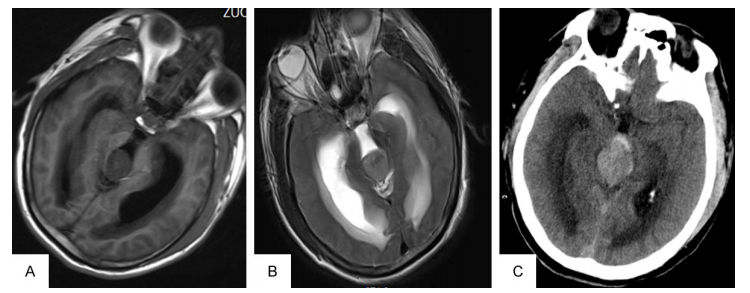

一名23歲男性,既往健康,有進行性頭痛、嘔吐和視力模糊病史。他在醫(yī)院就診前一天頭痛加劇。神經學檢查除了視力下降和雙側乳頭水腫外,未見其他異常。CT顯示松果體區(qū)等致密病變伴阻塞性腦積水(圖1A)。MRI顯示松果體區(qū)域腫瘤直徑2.6 cm*3.1 cm*2.9 cm, t1加權圖像低信號,t2加權圖像輕度高信號(圖1B)。采用德爾塔分流試劑盒進行腦室-腹腔分流手術以減輕患者的腦積水。分流術5小時后,病人惡化為深度昏迷狀態(tài),并無腦干反射。立即CT顯示三腦室大量瘤內出血,該腦室破裂進入側腦室(圖1C)。由于他的神經系統(tǒng)狀況不佳,沒有進行減壓手術,他后來去世了。

圖1。CT及橫t2加權MRI顯示松果體區(qū)腫瘤合并梗阻性腦積水(a及B)。CT顯示三腦室大量瘤內出血并破裂進入側腦室(C)。